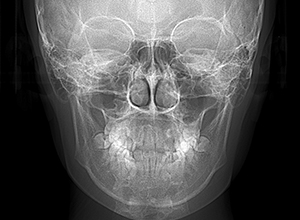

| X-Ray所見 | |

| セファロ所見 | 下顎頭はやや後方に位置しているが骨体部、下顎枝共に大きく上部構造体に対してバランスよく位置付いていた。中顔面は奥行きがあり下顔面高の高さは高くなかった。 |

| パノラマ所見 | 上顎両側第三大臼歯は欠損、下顎第三大臼歯は埋伏していた。 |